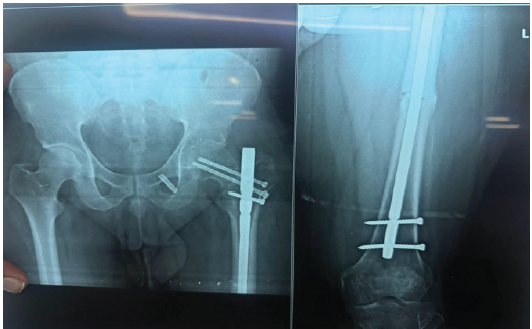

Figure 4: Immediate post-operative radiograph after the second surgery of the hip and full-length femur anteroposterior view showing miss-a-nail compression screws for the neck femur with fracture distraction reduced at the shaft.

Post-operatively patient was started with knee range of motion, bed-side sitting, and non-weight bearing with a walker. Serial X-rays were taken and it showed Good union at both the fracture site and NO avascular necrosis (AVN) changes in the head of the femur. After 2 months, the patient was advised to follow weight-bearing mobilization with the help of a walking cane and to continue knee and hip strengthening exercises. Patient is symptomatically better and has minimal pain over the operated limb.